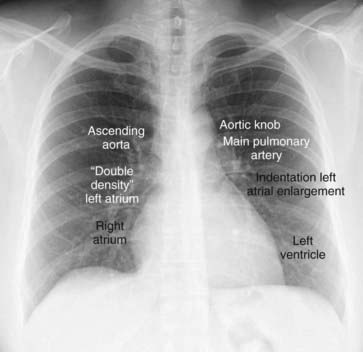

image The normal cardiac contours comprise a series of bumps and indentations visible on the frontal chest radiograph. They are demonstrated in Figure 9-6.

image

Figure 9-6 Normal cardiac contours seen in the frontal projection.

There are seven identifiable cardiac contours on the frontal chest radiograph. On the right side of the heart, the first contour is a low-density, almost straight edge visible just lateral to the trachea reflecting the size of the ascending aorta. Where the contour of the ascending aorta meets the contour of the right atrium, there is usually a slight indentation where the left atrium may appear when it enlarges. The right heart border is formed by the right atrium. On the left, the first contour is the aortic knob, a radiographic structure formed by the foreshortened aortic arch superimposed on a portion of the proximal descending aorta. The next contour below the aortic knob is the main pulmonary artery before it divides into a right and left pulmonary artery. Just below the main pulmonary artery segment there is normally a slight indentation where an enlarged left atrium may appear on the left side of the heart. The left ventricle forms the last contour of the heart on the left. The descending aorta almost disappears with the shadow of the spine.

imageKey points about the cardiac contours:

The ascending aorta should normally not project farther to the right than the right heart border (i.e., right atrium).

The aortic knob is normally less than 35 mm (measured from the edge of the air-filled trachea) and will normally push the trachea slightly to the right.

The normal left atrium does not contribute to the border of the heart on a nonrotated frontal chest radiograph.

An enlarged left atrium “fills-in” and straightens the normal concavity just inferior to the main pulmonary artery segment and may sometimes be visible on the right side of the heart as well.

Normally, the descending aorta parallels the spine and is barely visible on the frontal radiograph of the chest. When it becomes tortuous or uncoiled, it swings farther away from the thoracic spine towards the patient’s left (Fig. 9-7).